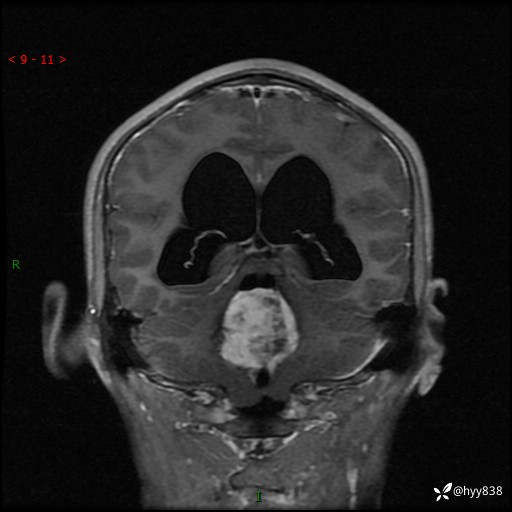

性别:男

年龄:17岁

简要病史:头痛伴间断性呕吐1月余,外院CT提示颅脑占位

颅脑MRI平扫+增强